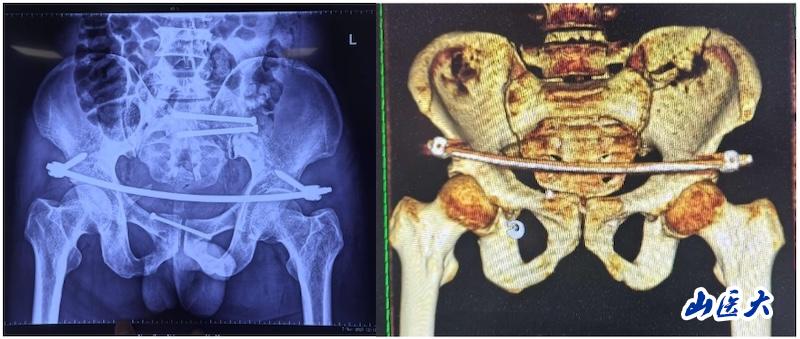

术中

据孙海钰介绍,骨盆髋臼骨折是一种严重的创伤,传统开放复位内固定术创伤大、恢复慢,而闭合复位则具有微创、出血少、恢复快等优点。随着医疗技术的不断进步,UCRT解锁复位技术结合天玑机器人及O-arm术中影像系统为骨盆骨折治疗提供了更加精准、微创的解决方案,该技术代表了当前骨盆骨折治疗的前沿方向。

术后